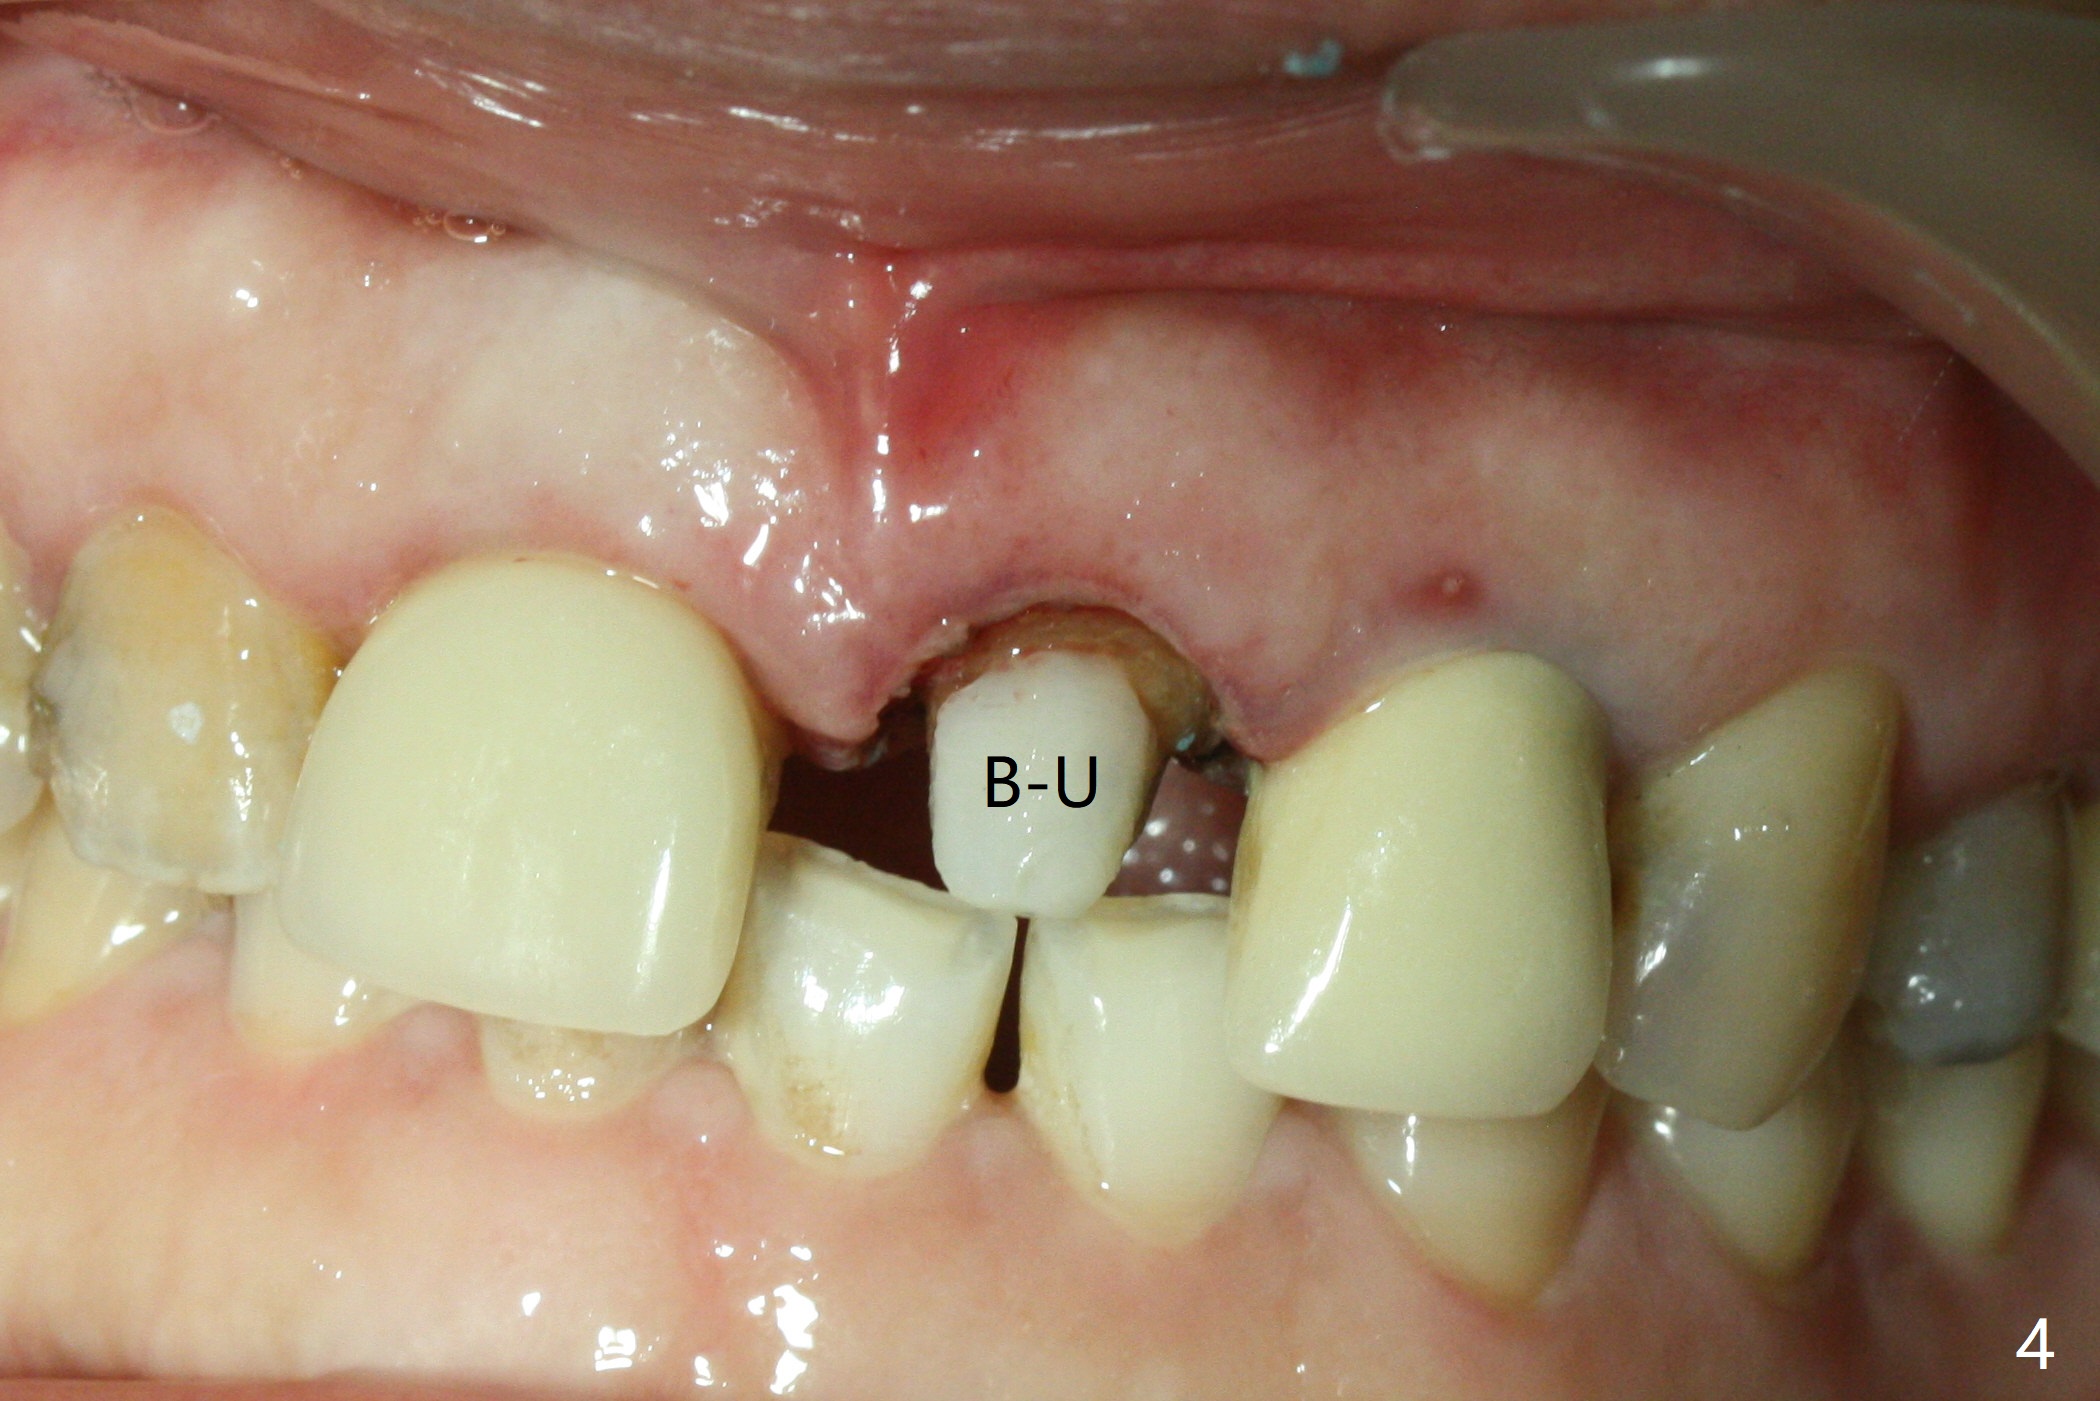

When the 44-year-old woman returns, the crown dislodges from #9 with palatal porcelain chip (Fig.1). Although the post is in place as compared to its dislodgement last visit, it is short and pointed (Fig.2,3 P). Because of the anterior deep bite (Fig.4), an implant restoration may not provide advantage; a new build-up is fabricated (B-U) for a new crown (Fig.5-6). The existing crown is reinserted for shade comparison (Fig.7 C). The gingiva at #8 and 9 is healthy, whereas that at #10 is not (Fig.8). PA taken 5 months later shows that the crown at #10 looks normal (Fig.9).